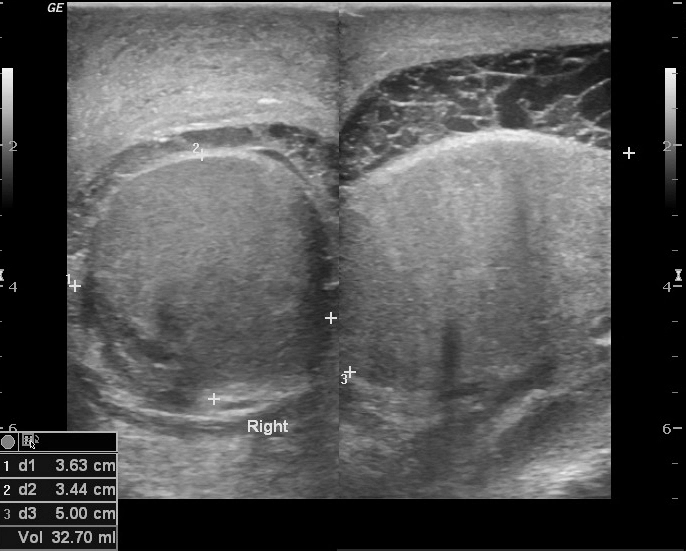

• Bìu và thừng tinh

• Bệnh lý viêm nhiễm

Áp xe thành bìu (Scrotal wall abscess)

16/03/2026